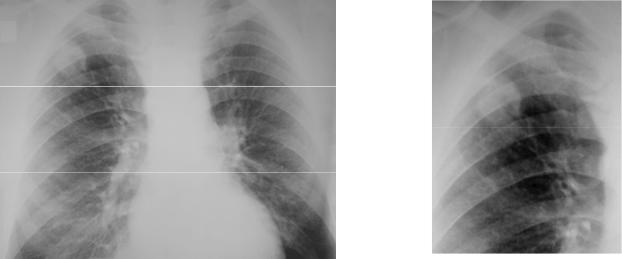

Иллюстрации по теме очагового и инфильтративного туберкулеза